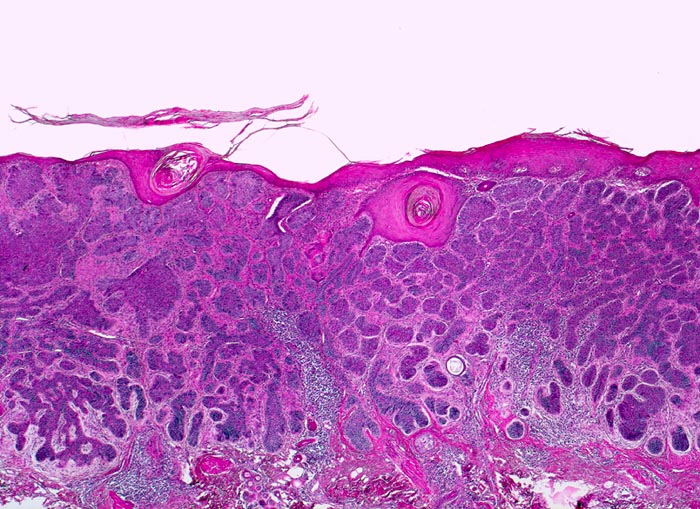

Basaliom

maligner Tumor

Haut, Kopf

Haut

Unmittelbar unterhalb der Epidermis liegen kompakte basophile verzweigte expansiv wachsende Zellplatten. Fokale Hyperkeratose der Epidermis. Am Rand des Tumors dichtes chronisches Entzündungsinfiltrat.

Derber weisser, leicht erhabener Knoten an der Nase.

Histologie

25